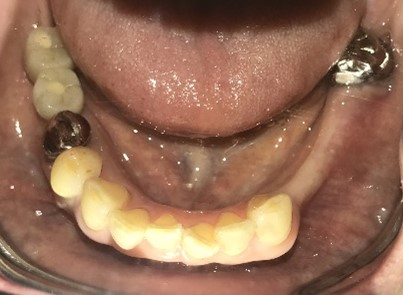

男性Kさん 50代(インプラント)

主訴

歯がグラグラするところ、むし歯のところ、しみるところ、被せ物がとれたところ、歯茎が腫れて血が出るところ、歯が抜けているところがある。すべて治したい。

治療内容

残っている歯を抜歯し、上下インプラント治療をしました。

所感

歯周病が進行している歯、むし歯が進行している歯がほとんどで、レントゲンを撮り、詳しく診てみると、ほとんどの歯を保存することができないことがわかりました。抜歯後は、入れ歯かインプラントの方法があります。治療開始前に患者さんに詳しく現状を説明し、治療法についてじっくり相談しました。自分の歯と同じような感覚で食事できるインプラント治療を選択されました。治療後、表情がとても明るくなり、口元がとても自然で10歳以上若返ったように感じました。「時間はかかりましたが、インプラントにして本当に良かったです!」と素晴らしい笑顔でお話ししてくださいました。